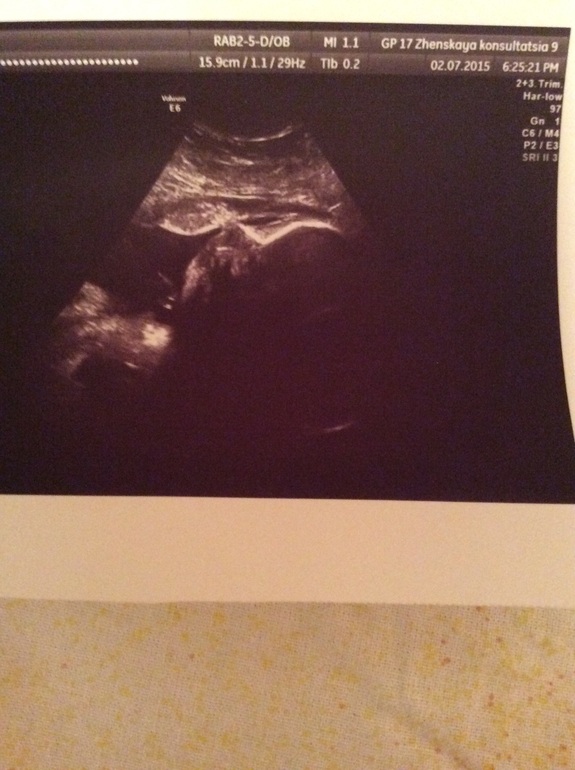

Были сегодня на УЗИ , нам по срокам 32.2 , но недельку мы опережаем срок , весим мы уже 1800 кг , что меня очень радует !

Малыш слава богу лег как надо , а то до этого все на попе сидел , по УЗИ с нами ттт все хорошо, мы активные и здоровые! Как же приятно это слышать , с плацентой все хорошо , поднялась слава богу с водами тоже все отлично , обвитая нет

развиваемся как нужно ! А вот и фото наше, честно всегда думала когда пишут что на кого то похож этопреувеличение , но сегодня когда показали малыша это точно наш папа, такой же курносый!!! И фото в студию , моего сладкого мальчика